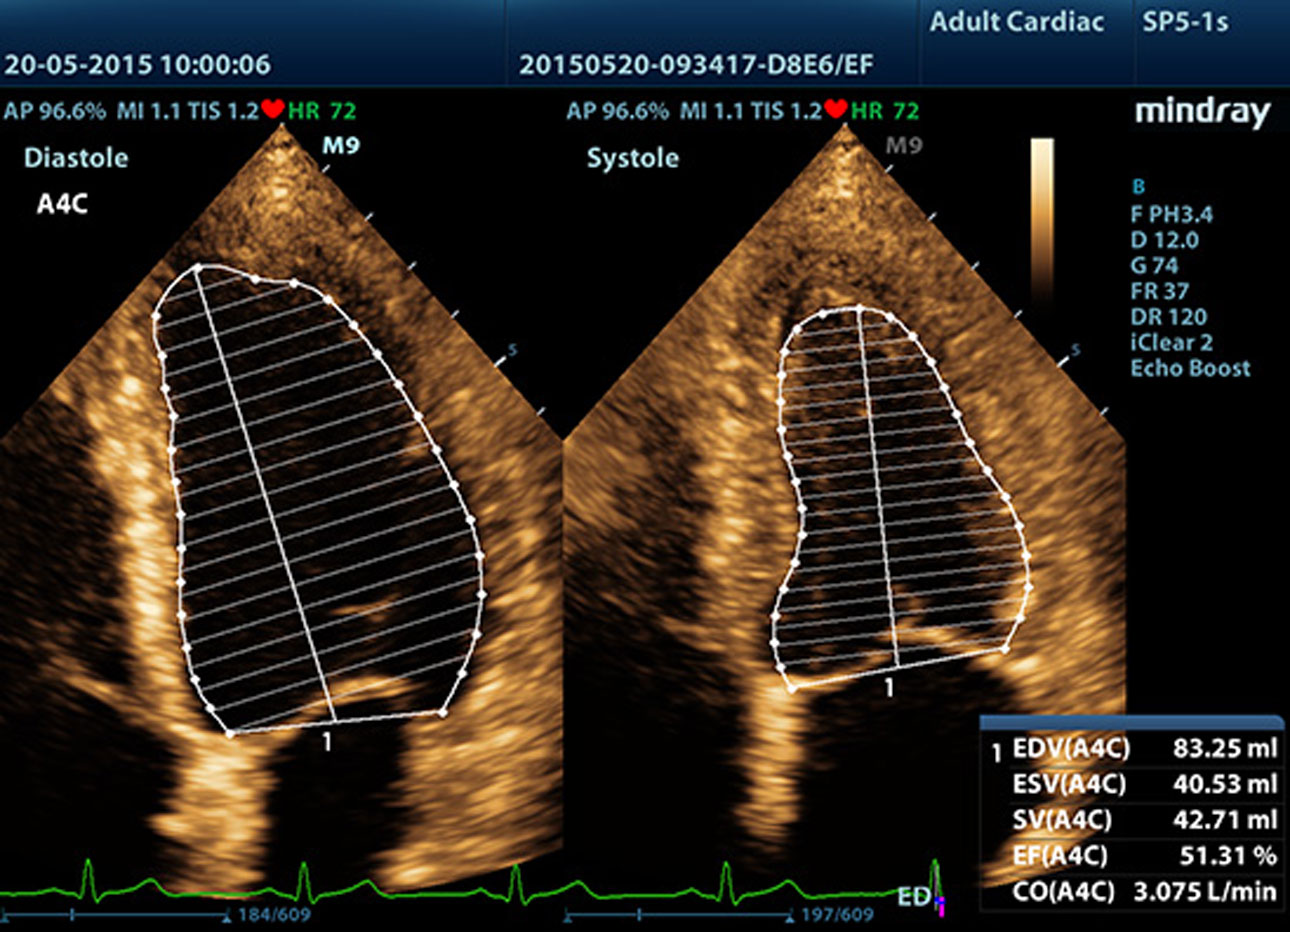

AutoEF

Intelligent way to analyze 2D echo clips to automatically recognize diastole/systole frames and output EDV/ESV/EF etc. results by Simpson method.